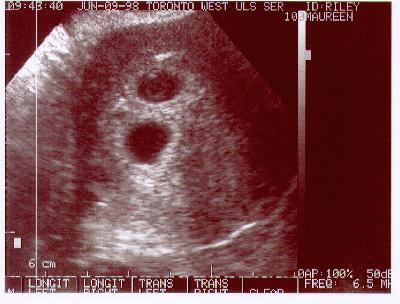

June 9, 1998

5 weeks, 5 days

This is the first indication that if all goes well, we will be having twins. Yes, the image above shows 2 yolk sacs.